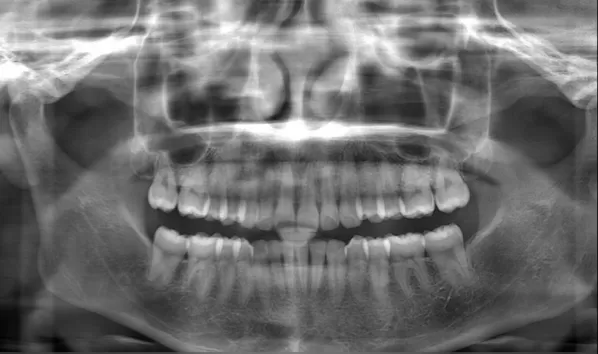

Female, 25 years old. Chief complaint: protruding and misaligned teeth, requiring orthodontic treatment.

X-rays before treatment

[Panoramic Radiography/Lateral Cephalogram]